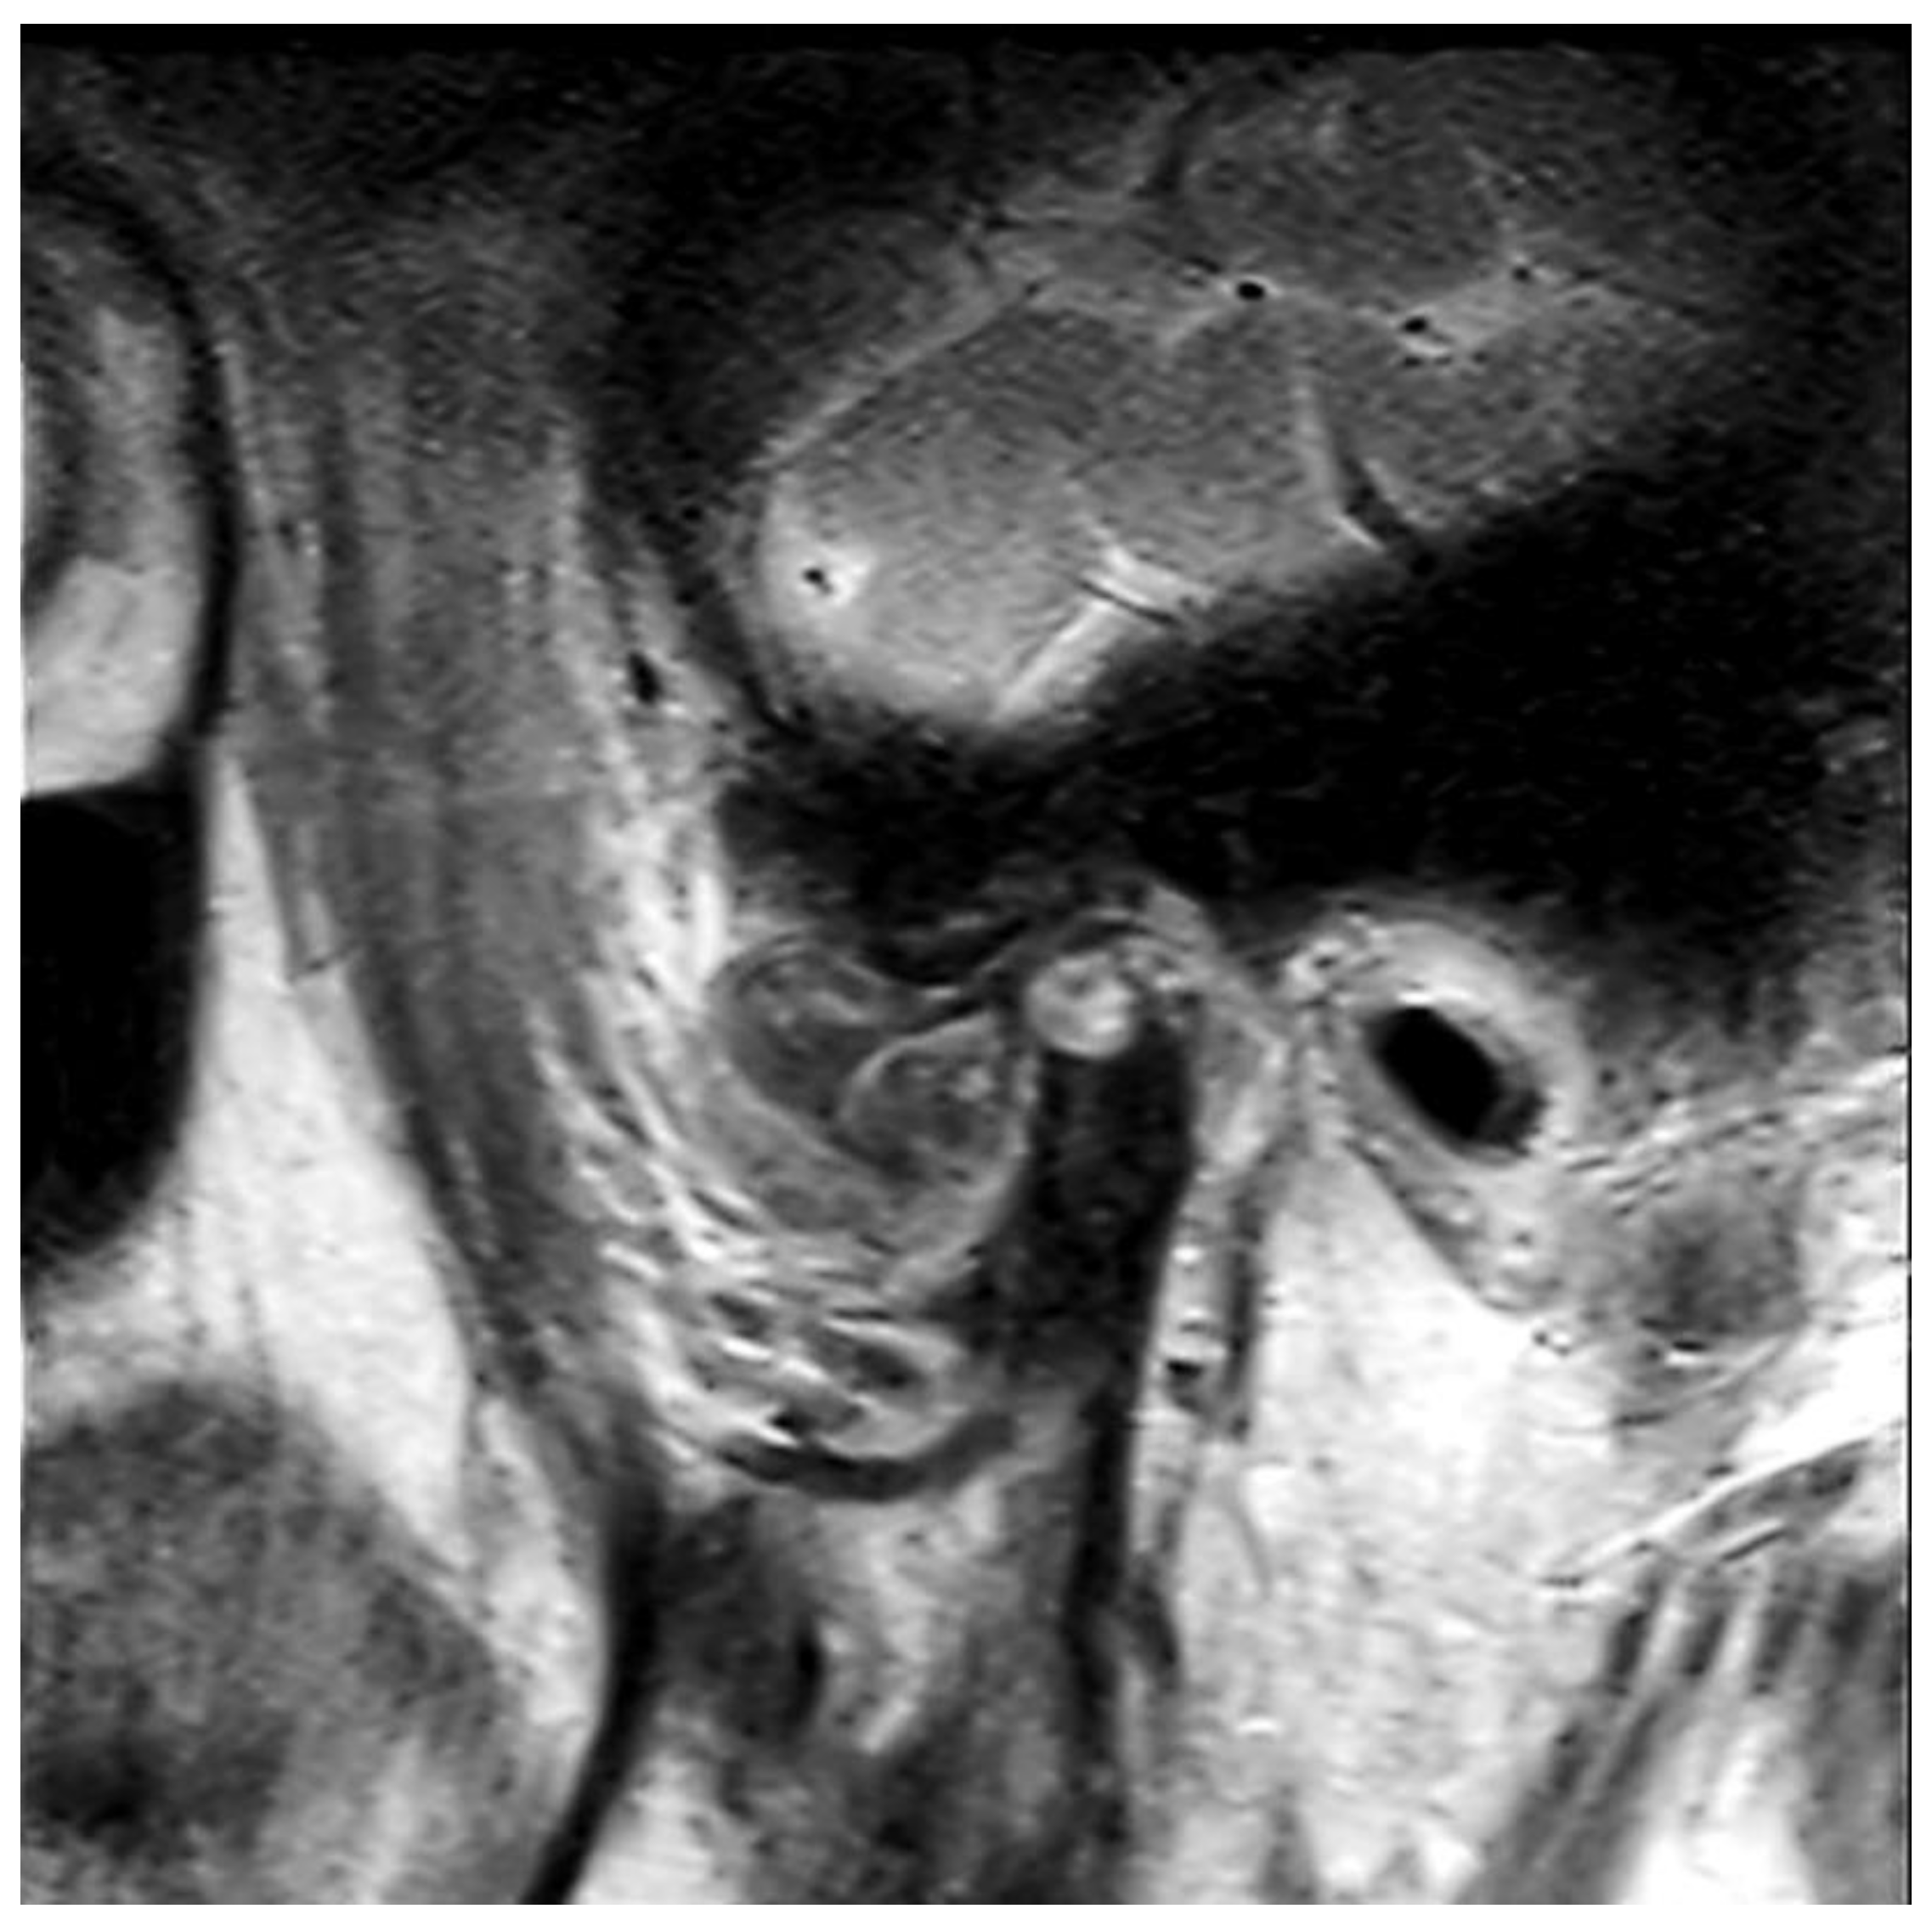

2.2. Pathological Findings